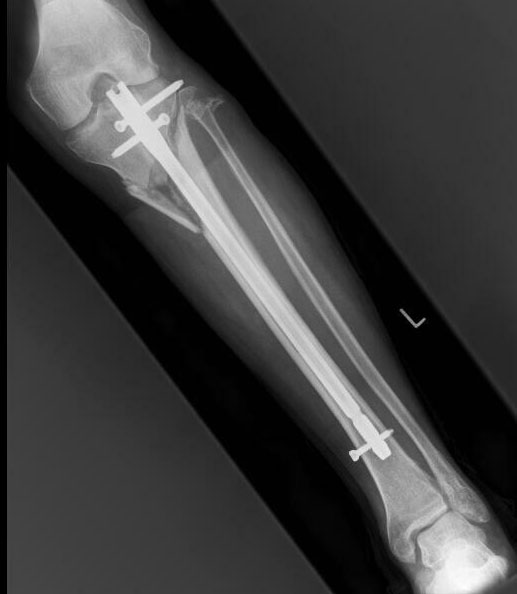

From flickr.com

Broken Leg with Rod XRay Flickr Photo Sharing! Titanium Rod In Leg Infection I have titanium buttress plate in my proximal tibia since 13 years. Zhuang y., ren l., zhang s., wei x., yang k., dai k. I am concern about future complications in my old age as i. There is no consensus or clear. Titanium and its alloys have emerged as excellent candidates for use as orthopedic biomaterials. Nevertheless, there are often. Titanium Rod In Leg Infection.

Titanium rod through Tibia leg bone. Ouch Titanium Rod In Leg Infection Zhuang y., ren l., zhang s., wei x., yang k., dai k. I have titanium buttress plate in my proximal tibia since 13 years. The first report of cutaneous hypersensitivity caused by a metallic orthopedic implant was a 1966 case report by foussereau. Titanium and its alloys have emerged as excellent candidates for use as orthopedic biomaterials. There is no. Titanium Rod In Leg Infection.